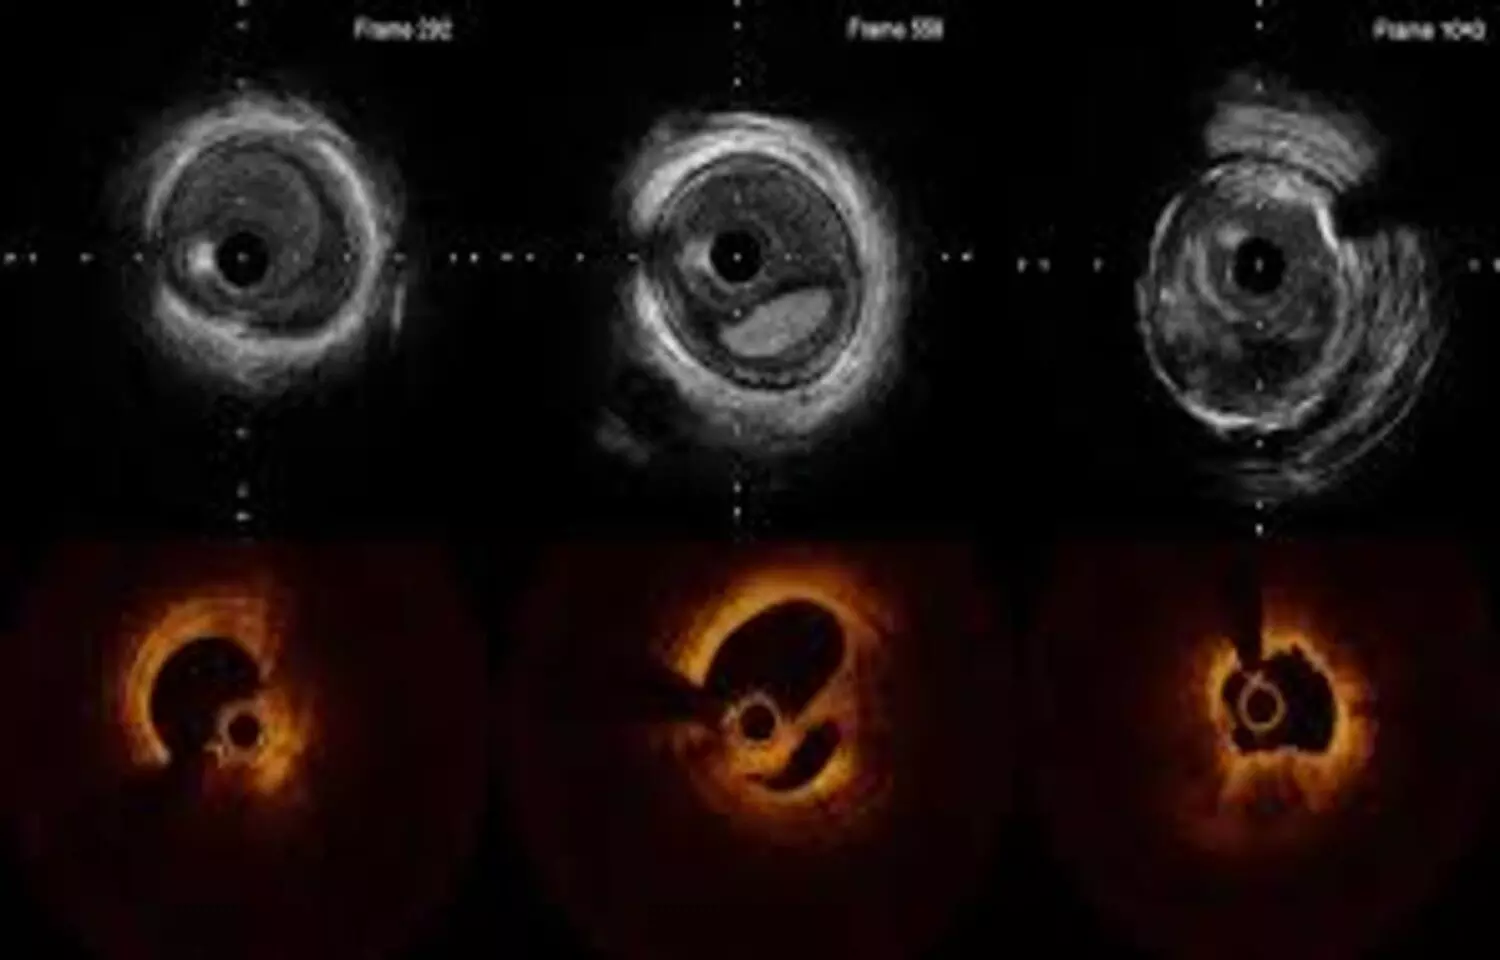

Five-year follow-up data from the RENOVATE-COMPLEX-PCI trial show that intravascular imaging–guided percutaneous coronary intervention leads to better clinical outcomes in patients with complex coronary lesions. Earlier results (median follow-up 2.1 years) demonstrated a 36% relative reduction in target-vessel failure—including cardiac death, target-vessel myocardial infarction, or clinically driven target-lesion revascularization—compared with angiography-guided percutaneous coronary intervention. In addition, target-vessel MI or cardiac death decreased by 37%, and cardiac death alone by 53%, highlighting the long-term benefit of intravascular imaging guidance.Data regarding long-term outcomes of intravascular imaging-guided percutaneous coronary intervention (PCI) for complex coronary artery lesions, compared with angiography-guided percutaneous coronary intervention, remain limited.The authors sought to present long-term clinical outcomes of intravascular imaging-guided percutaneous coronary intervention compared with angiography-guided percutaneous coronary intervention in patients with complex coronary artery lesions. Eligible patients with complex coronary artery lesions were randomly assigned 2:1 to undergo intravascular imaging-guided percutaneous coronary intervention or angiography-guided percutaneous coronary intervention in this prospective multicenter open-label superiority trial performed in South Korea. The primary endpoint was a composite of cardiac death, target vessel-related myocardial infarction, or clinically driven target vessel revascularization.Results: A total of 1,639 patients underwent randomization with 1,092 assigned to imaging-guided percutaneous coronary intervention and 547 assigned to angiography-guided percutaneous coronary intervention. At a median follow-up of 5.3 years (Q1-Q3: 4.4-6.2 years), the primary endpoint occurred in 109 of 1,092 patients (10.5%) in the intravascular imaging-guided percutaneous coronary intervention group and 78 of 547 patients (14.9%) in the angiography-guided percutaneous coronary interventiongroup (HR: 0.68; 95% CI: 0.51-0.91; P = 0.009). Cardiac death or target vessel–related myocardial infarction occurred in 78 patients (7.6%) in the intravascular imaging-guided percutaneous coronary intervention group and in 56 patients (10.7%) in the angiography-guided percutaneous coronary intervention group, clinically driven target vessel revascularization in 45 (4.4%) and 32 (6.2%), and definite stent thrombosis in 1 (0.1%) and 4 (0.7%), respectively. There were no apparent differences in procedure-related safety events between the groups.In patients with complex coronary artery lesions undergoing percutaneous coronary intervention, intravascular imaging guidance reduced the risk of a composite of cardiac death, target vessel–related myocardial infarction, or clinically driven target vessel revascularization at median follow-up of 5.3 years, compared to angiography guidance. Reference:Lee, J, Kim, O, Song, Y. et al. Intravascular Imaging- vs Angiography-Guided Complex PCI: 5-Year Outcomes From a Randomized Trial. JACC. null2026, 0 (0) .https://doi.org/10.1016/j.jacc.2026.01.035Keywords:Intravascular, Imaging, Improve, Long-Term, Outcomes, Complex PCI, Study, Lee, J, Kim, O, Song, Y.